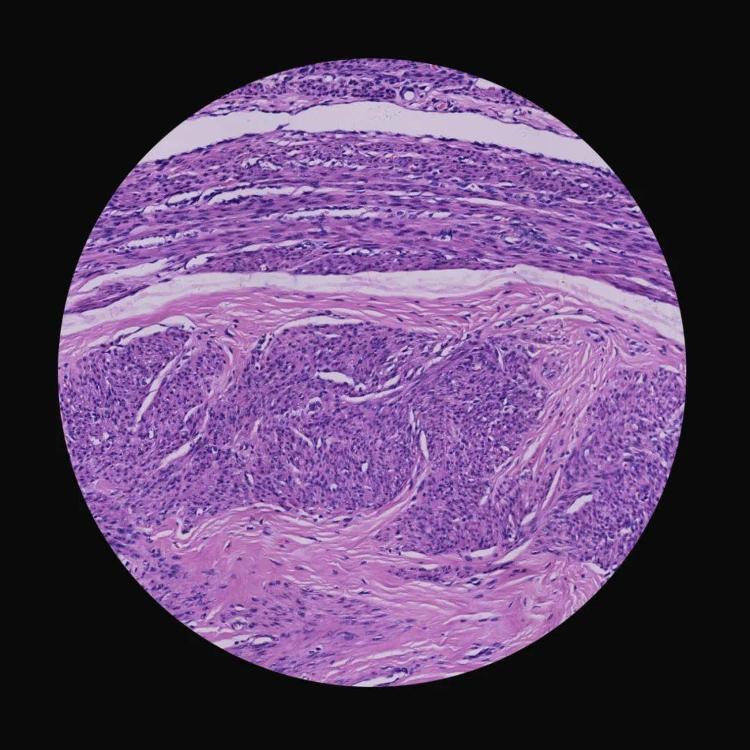

《生死较量》(组照) 李元鹏 摄影